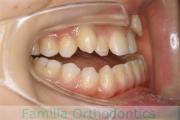

No.22V-299

- 上顎前突

- 叢生

- 30歳

- 女性

- 上:

- 44

- 下:

- 主な使用装置:

- FEA 022

- 治療にかかった費用:

- 90万円

上の出っ歯、口が閉じにくい、下の前歯のガタガタを治したいということで来院されました。上顎から左右小臼歯を、下の前歯は凹凸が非常に強いので、こちらから一本抜歯を行いました。2年強、30回程度の通院が必要でした。

成人になってからの叢生(でこぼこ、凹凸、ガタガタ)は、保定をしっかりしないと後戻りをしてしまうリスクが高いです。